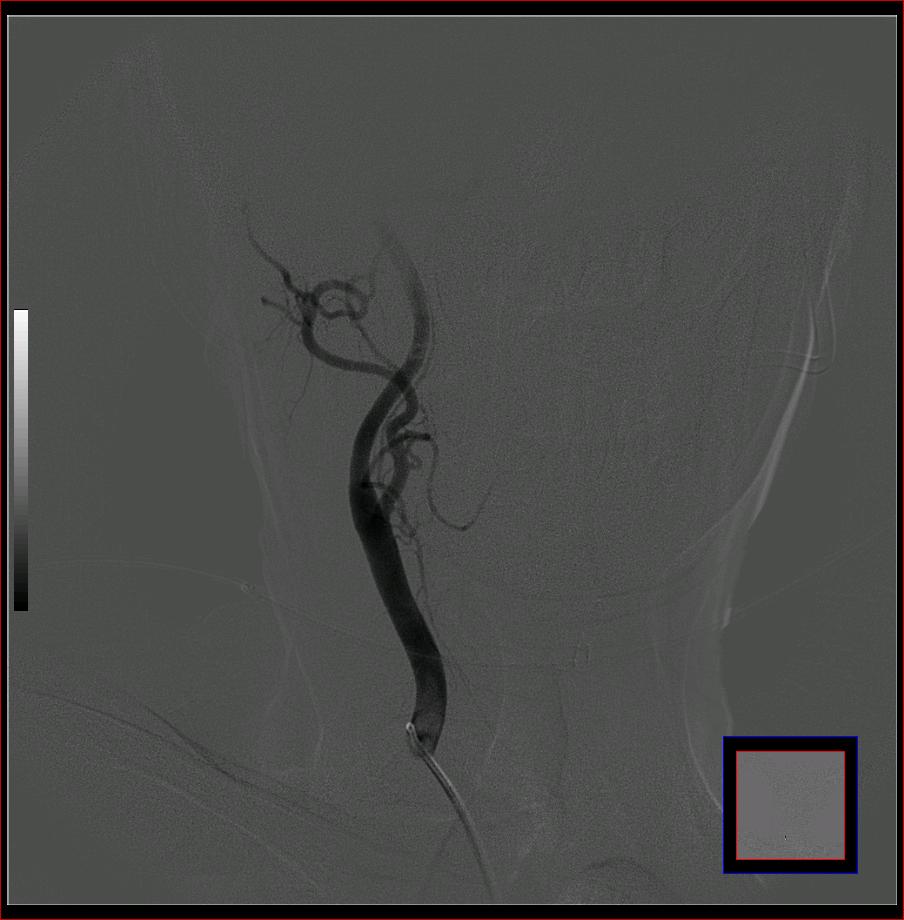

标题: DSA0121:脑血管造影

男,65岁,肢体无力。

左侧大脑中动脉水平段狭窄.

右侧大脑前a缺如.左侧大脑中动脉m1段狭窄,远端分支分布稀疏.

前交通或稍远端动脉瘤要仔细查,左大脑中动脉狭窄要鉴别,有可能是痉挛,因为造影导管插得稍深啦。其它就是供血动脉变异较大